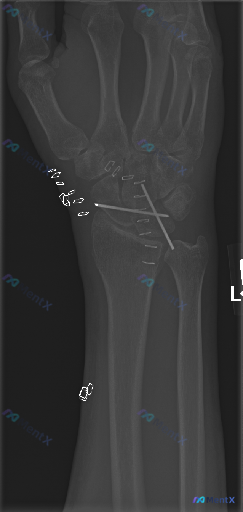

左侧腕关节正位X线:术后改变之外,还需要重点关注哪些异常?

整理到一份左侧腕关节正位X线的影像资料,情况如下: - 患者有腕骨骨折手术史 - 影像显示舟骨与月骨区域有交叉克氏针内固定,针尾位于桡侧软组织内 - 舟骨及相关腕骨的骨皮质轮廓尚完整,因金属伪影遮挡,隐匿性骨折线排查受限 - 桡侧皮下及近端软组织内可见散在多个小点状高密度影 - 腕骨间排列尚可,桡腕...